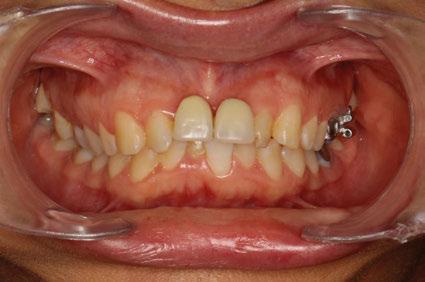

–Implantología monofásica, una herramienta más en Rehabilitación oral, por el Dr. Carlos Polis Yanes y cols. [78]

–Implantes híbridos en pacientes con antecedentes de periodontitis, por el Dr. Antonio Arnau y cols. [90]

–Implante inmediato en incisivo lateral superior con técnica de «Socket Shield» y acceso vestibular para legrado de la lesión periapical, por el Dr. Ignacio Tormo Jiménez y cols. [106]